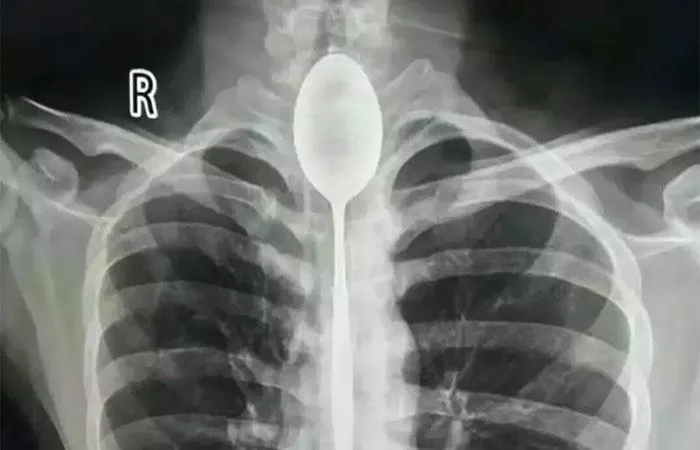

Хоч у горлі цього чоловіка була ложка, його це не дуже турбувало

Фото Xinjiang Meikuang General Hospital